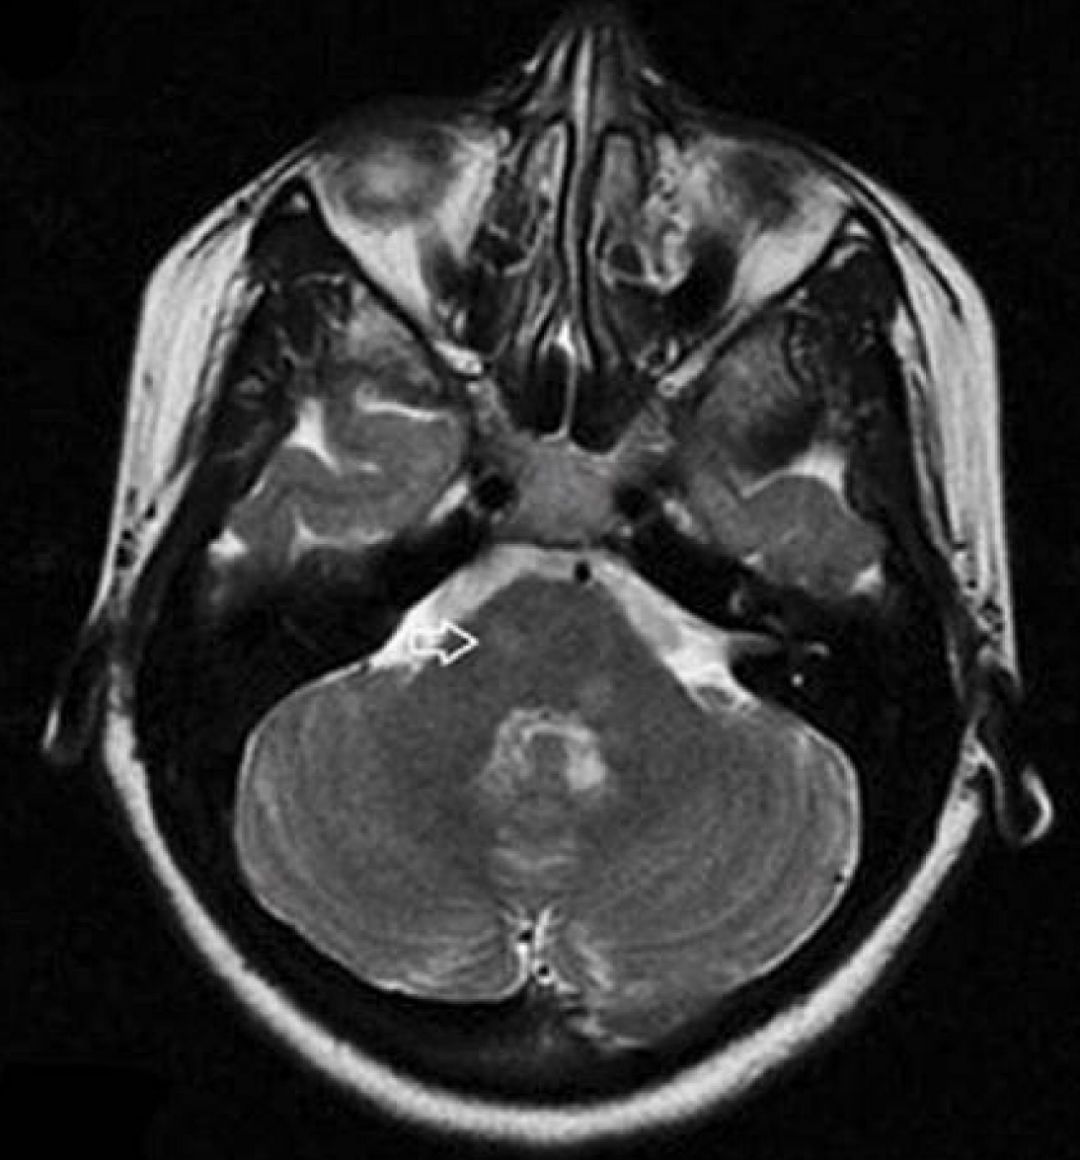

男性,50岁。“吞咽困难、右侧肢体无力4天”入院。查体:右侧Horner征+, 咽反射消失。右侧共济运动不稳。

答案:特殊类型延髓梗死——Opalski综合征。

Opalski综合征的临床表现为延髓背外侧综合征(即Wallenberg综合征)伴有同侧肢体轻偏瘫,曾被认为是延髓背外侧综合征的变异。定位于延髓背外侧中下部。MR影像上除延髓背外侧表现为DWI高信号外,肢体轻瘫同侧的小脑后下动脉和(或)椎动脉闭塞较具特征性。本病例旨在提醒大家,若患者出现显著吞咽困难伴有偏瘫时,不要忘了病灶可能在偏瘫同侧,这对选择性动脉溶栓很有指导意义。